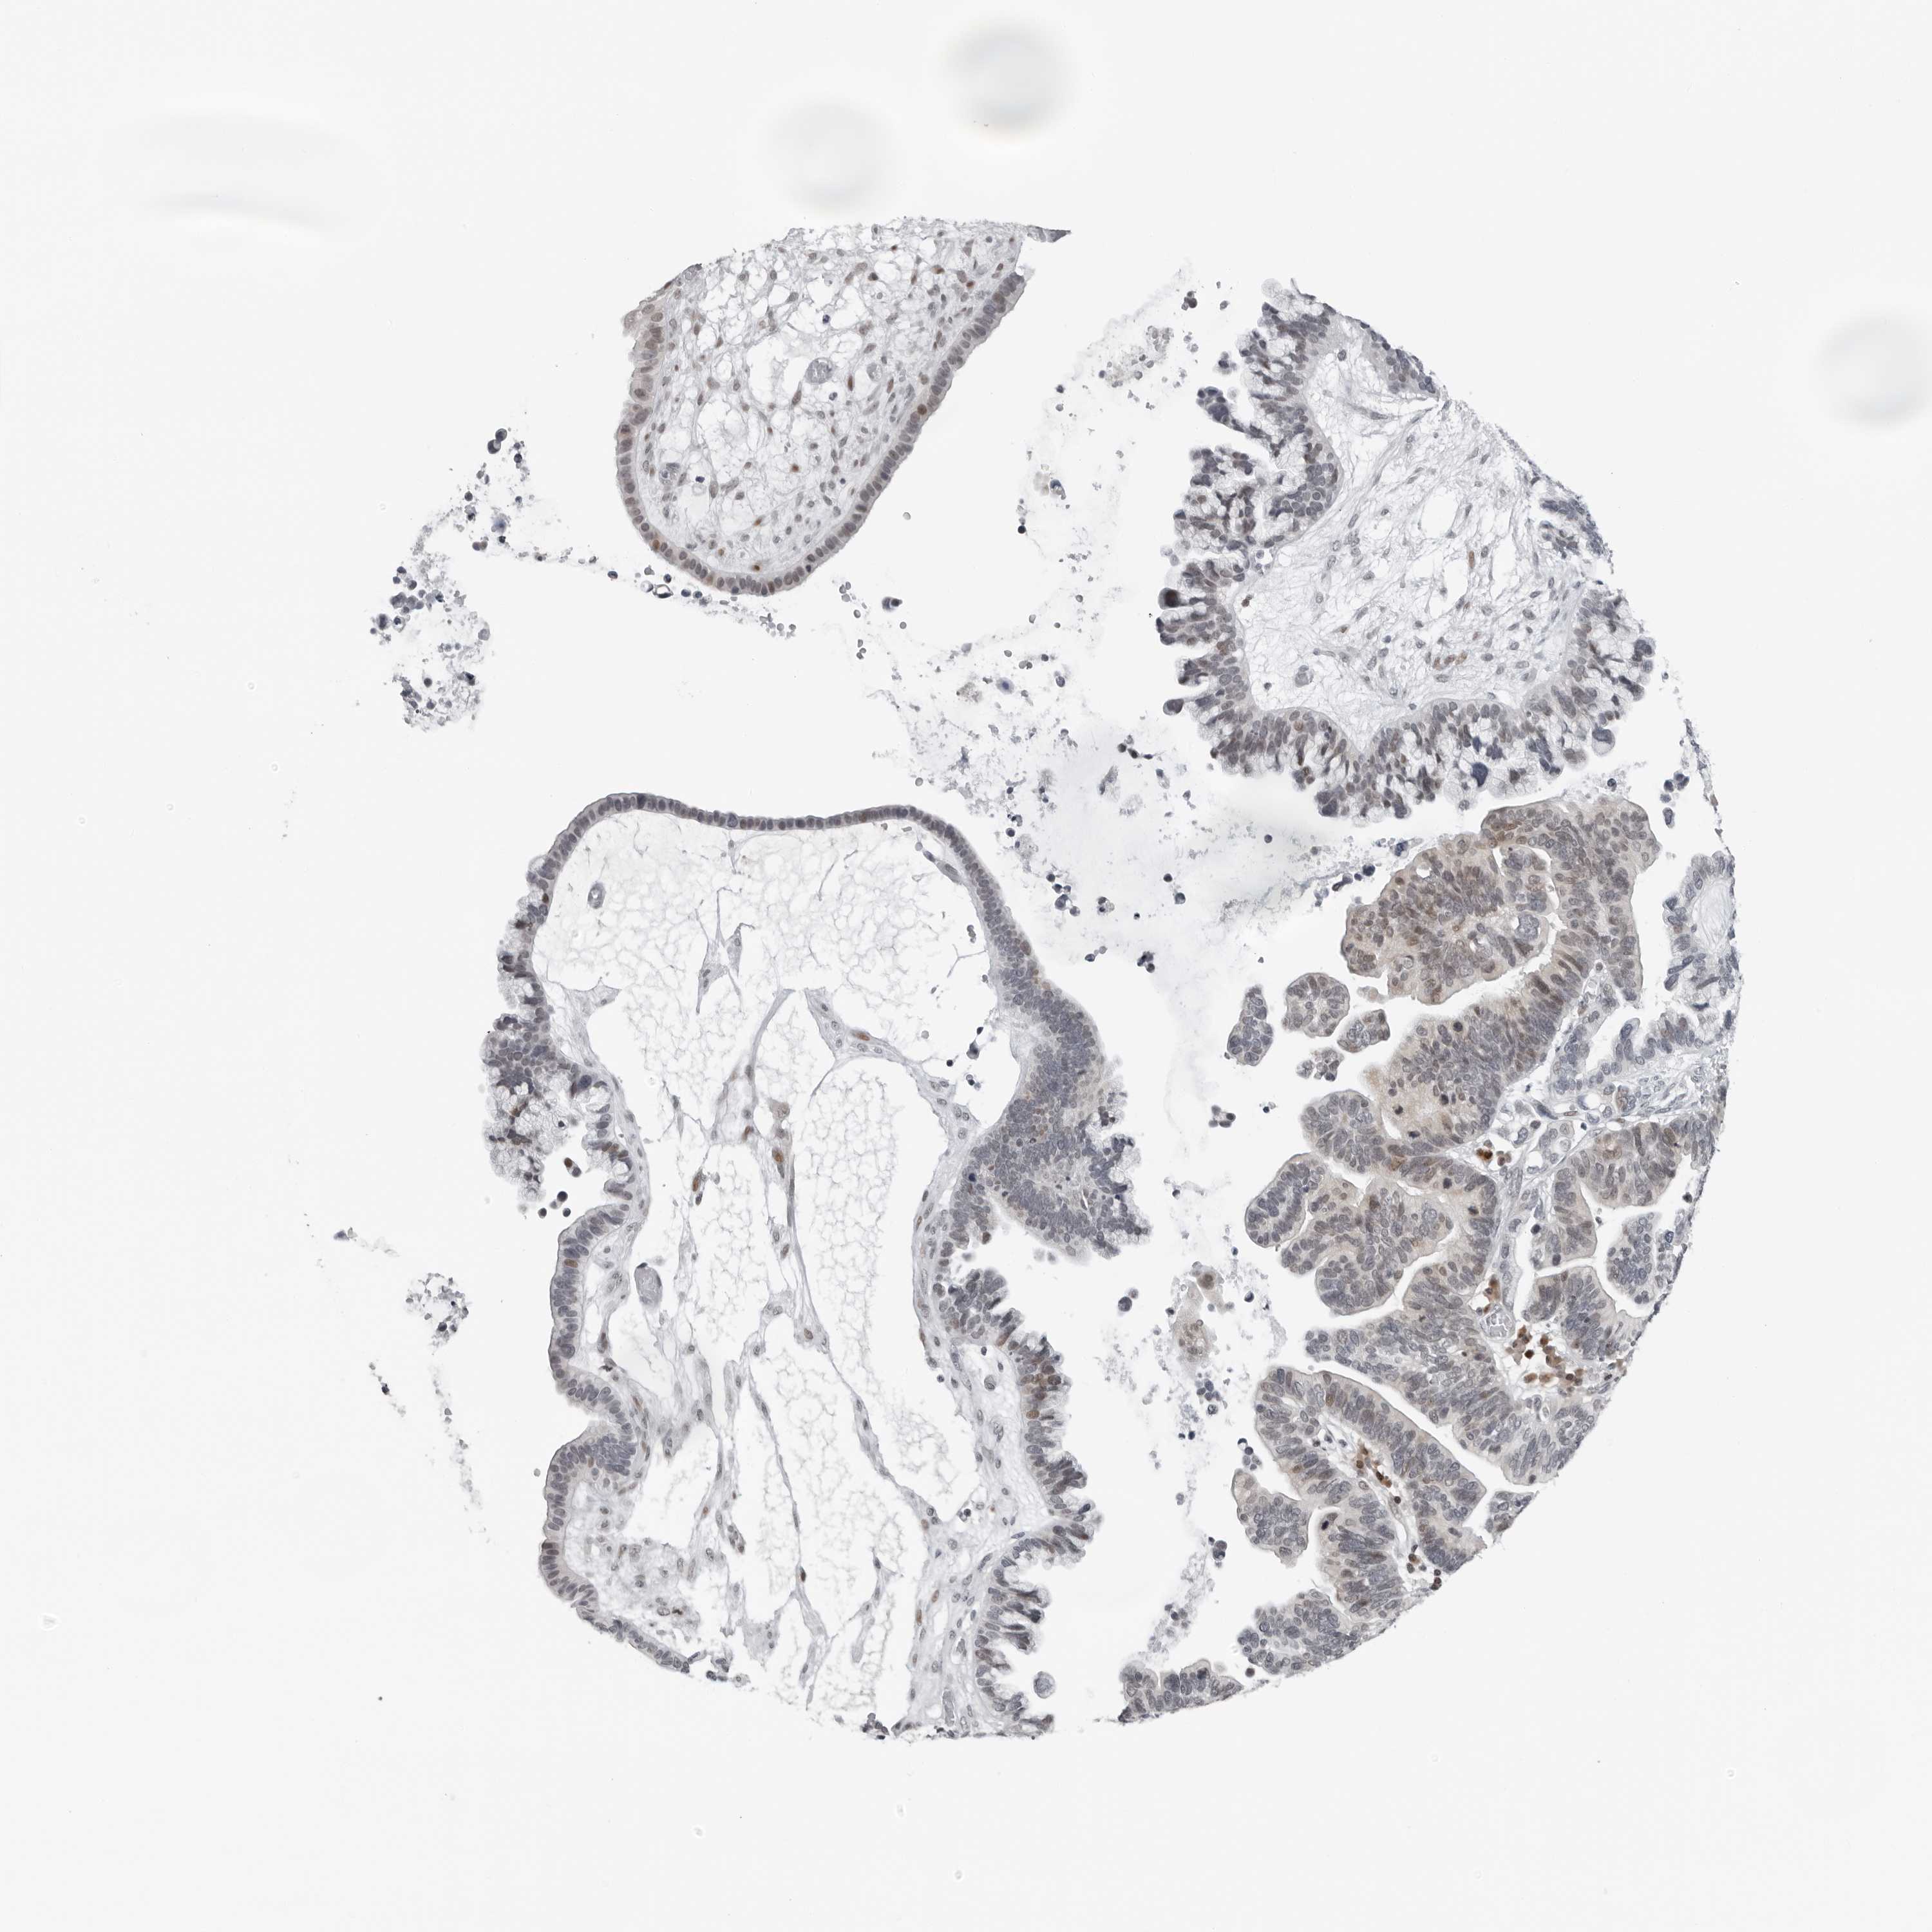

OVARIAN CANCER - Protein expressioni

A mouse-over function shows sample information and annotation data. Click on an image to view it in a full screen mode. Samples can be filtered based on level of antibody staining by selecting one or several of the following categories: high, medium, low and not detected. The assay and annotation is described here.

Note that samples used for immunohistochemistry by the Human Protein Atlas do not correspond to samples in the TCGA dataset.

Antibody stainingi

Antibody staining in the annotated cell types in the current human tissue is reported as not detected, low, medium, or high, based on conventional immunohistochemistry profiling in selected tissues. This score is based on the combination of the staining intensity and fraction of stained cells.

Each image is clickable and will lead to virtual microscopy that enables deeper exploration of all samples and also displays staining intensity scores, fraction scores and subcellular localization as well as patient and tissue information for each sample.

Antibody HPA024313

Antibody HPA027983

Antibody HPA028628

Cystadenocarcinoma, serous, NOS

Carcinoma, endometroid

Cystadenocarcinoma, mucinous, NOS

Carcinoma, NOS